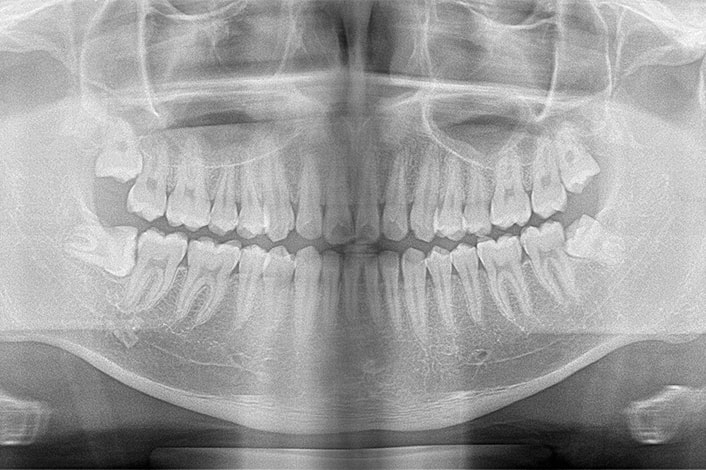

・レントゲンを撮影してより詳しく検査

むし歯チェック(5歳以降・目視とレントゲンによるダブルチェック)

お子さんの歯は、大人よりもむし歯が進行しやすいだけでなく、見た目だけでは進行度が分かりにくいという特徴があります。伊藤歯科クリニックでは、「見えるむし歯だけ治す」のではなく、「将来むし歯になりにくい口の環境を育てる」ことを大切にしています。

そのために行っているのが、目視とレントゲンによるダブルチェックです。

ダブルチェックのメリット

目視で発見できるむし歯は、じつは全体の約7割ほど。歯と歯の間などの入り組んだ場所は、丁寧に見てもどうしても限界があります。

一方でレントゲンでは、歯と歯の間のむし歯は分かりやすい反面、小さな初期むし歯は写りにくいという弱点があります。

この二つを組み合わせることで、どちらか一方では見逃しやすいむし歯を早期に発見でき、むし歯発見の精度が大幅に上がります。

早く見つかれば、削らずに守る選択肢も広がります。